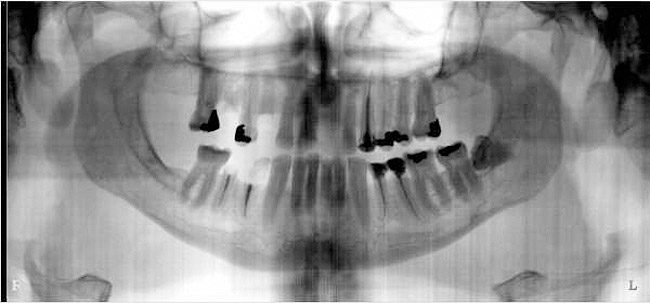

Figure 11a  Insufficient crown height space for bar overdenture because of the vertical dimension of the mandible.

Figure 11a

Figure 11b  Osteoplasty performed at the time of implant placement to gain sufficient crown height space.

Figure 11b